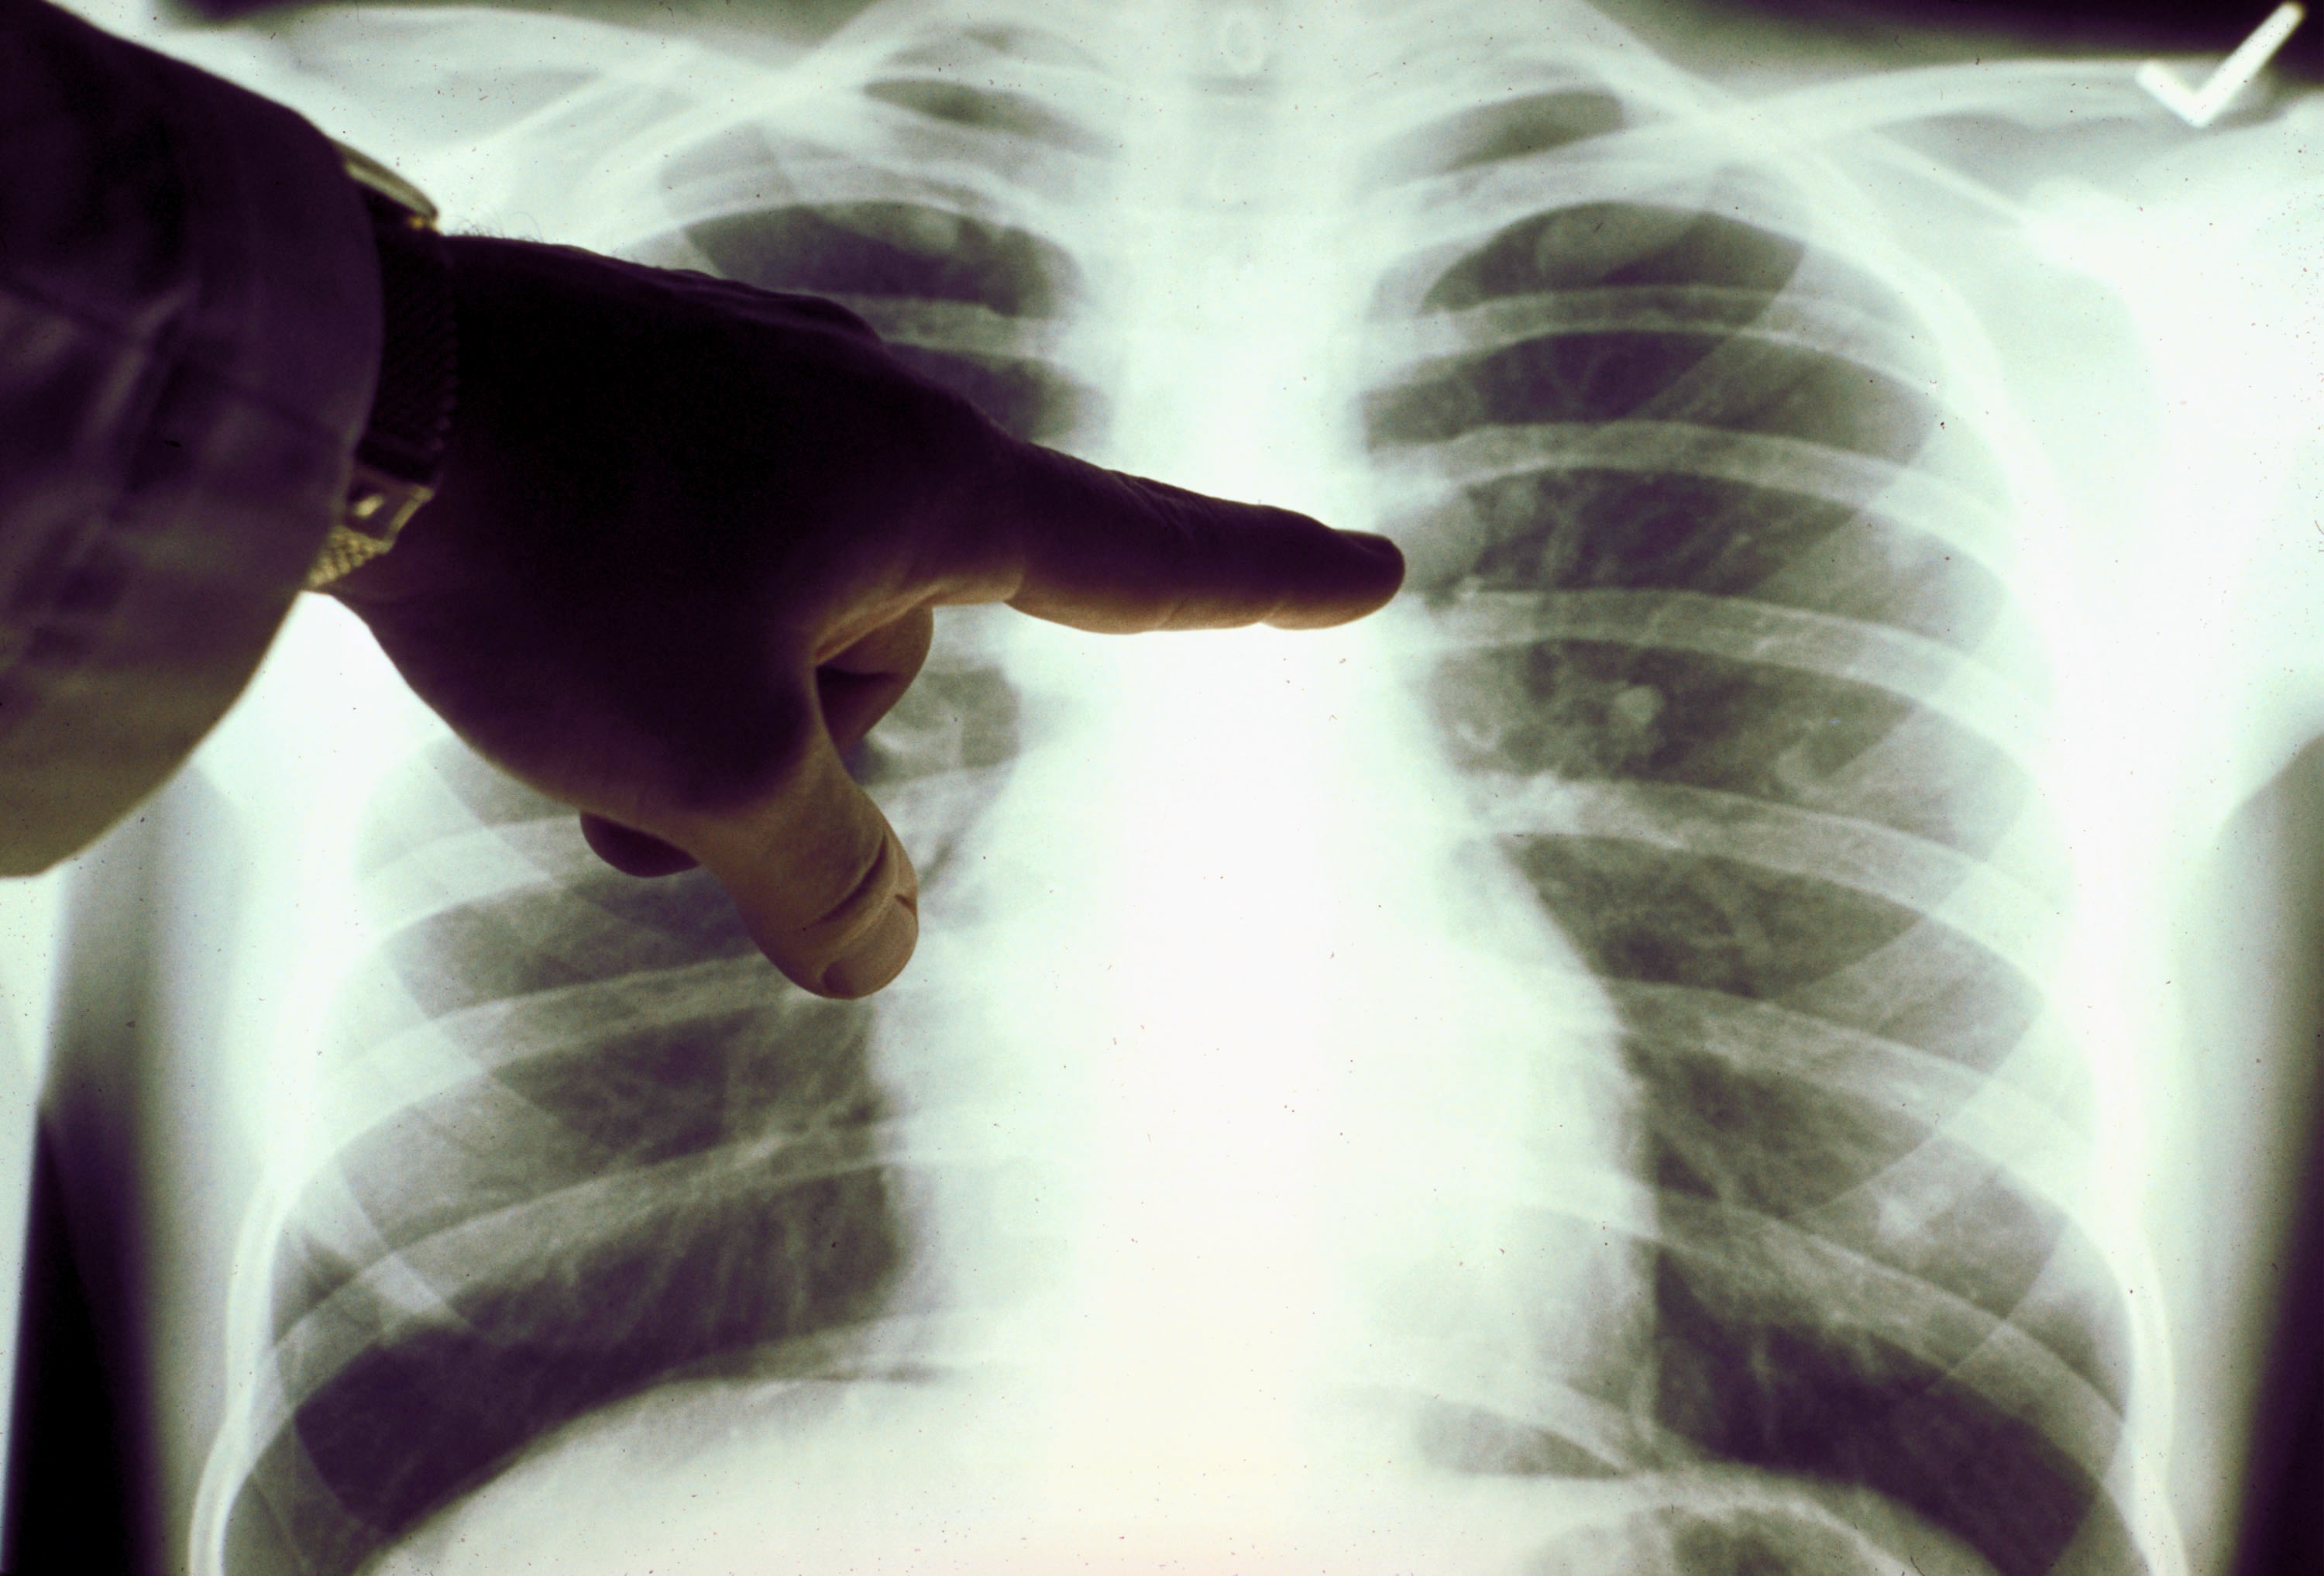

Симптомы и признаки туберкулеза: как распознать заболевание

Раздел: Визуальные уроки